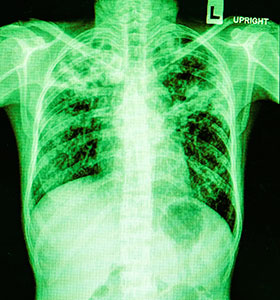

Se requiere la realización de una radiografía de tórax ante la sospecha de una neumonía para poderla diagnosticar. Las neumonías extrahospitalarias típicas, se presentan con un patrón característico que es el de una condensación alveolar con broncograma aéreo (80% de los casos en forma de crepitantes pulmonares). Las atípicas se presentan radiológicamente con un infiltrado intersticial, siendo característica la disociación clínica radiológica (la exploración física suele ser normal).

No existen patrones radiográficos concretos que permitan identificar el agente infeccioso.